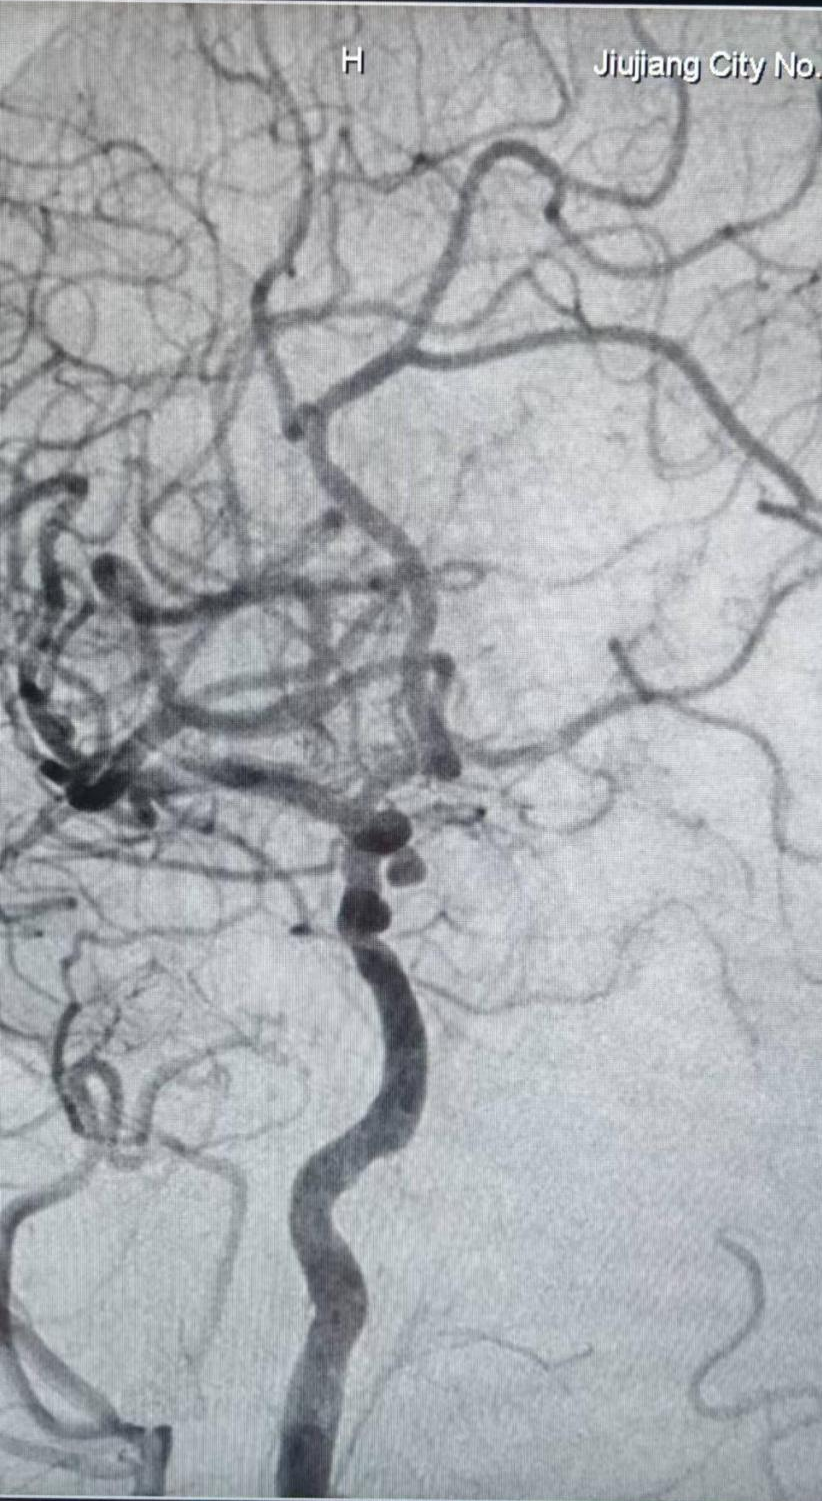

入院后,神经外科二组陈进主任团队立即为李女士完善相关检查。经过充分术前准备,为其实施全麻下“脑血管造影+经导管颅内动脉瘤栓塞术”。术中3D血管造影显示,动脉瘤位于右侧颈内动脉眼段,大小约3.94mm*3.53mm,瘤颈宽约2.75mm,瘤颈相对偏窄。

术前脑血管造影

3D-DSA造影示:右侧颈内动脉C6段动脉瘤